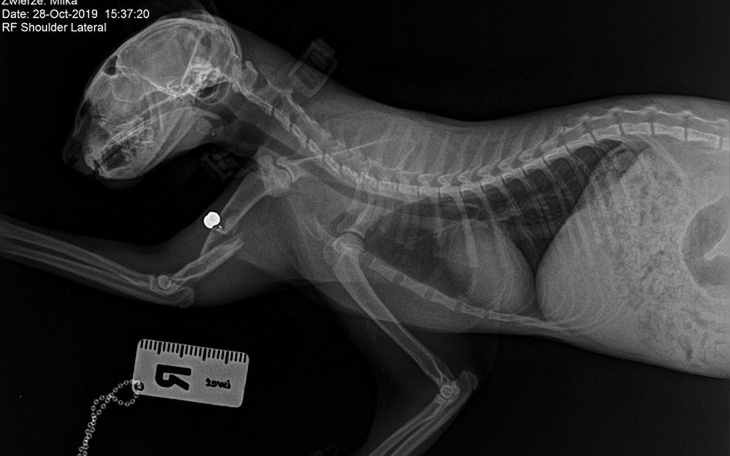

Śrut 5,5 mm, całe szczęście za zatrzymał się na kości ramiennej, kilka cm w stronę ogona i przeszył by Milke na wylot

Ktoś chciał zastrzelić Milkę. Milka jak każdy kot uwielbiała łazić po okolicy, aż w końcu trafiła na idiotę z wiatrówką. Przeszła już jedną operację łapy, która kosztowała kilkaset złotych, ale niestety jak to kot, wymknęła się niepostrzeżenie z domu i wróciła z jeszcze bardziej strzaskaną.